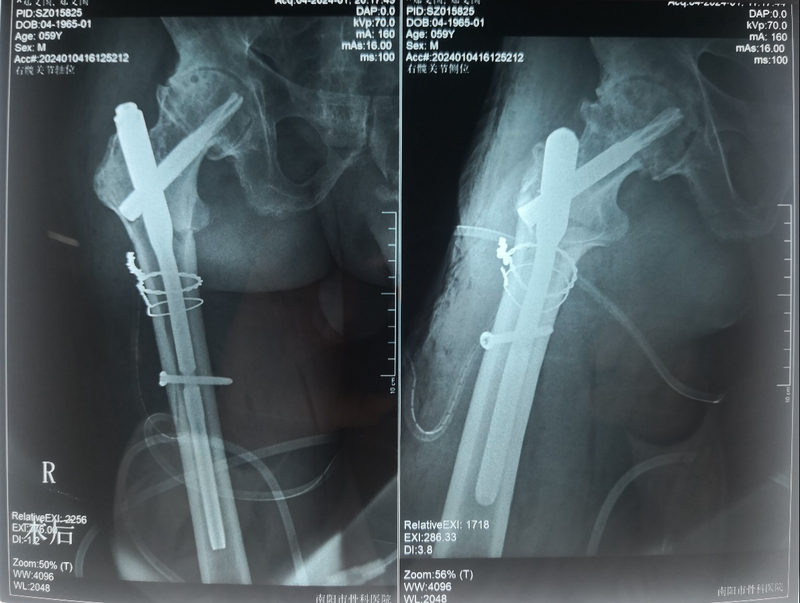

9.术后复查X线片,解剖复位,内固定物固定牢固。